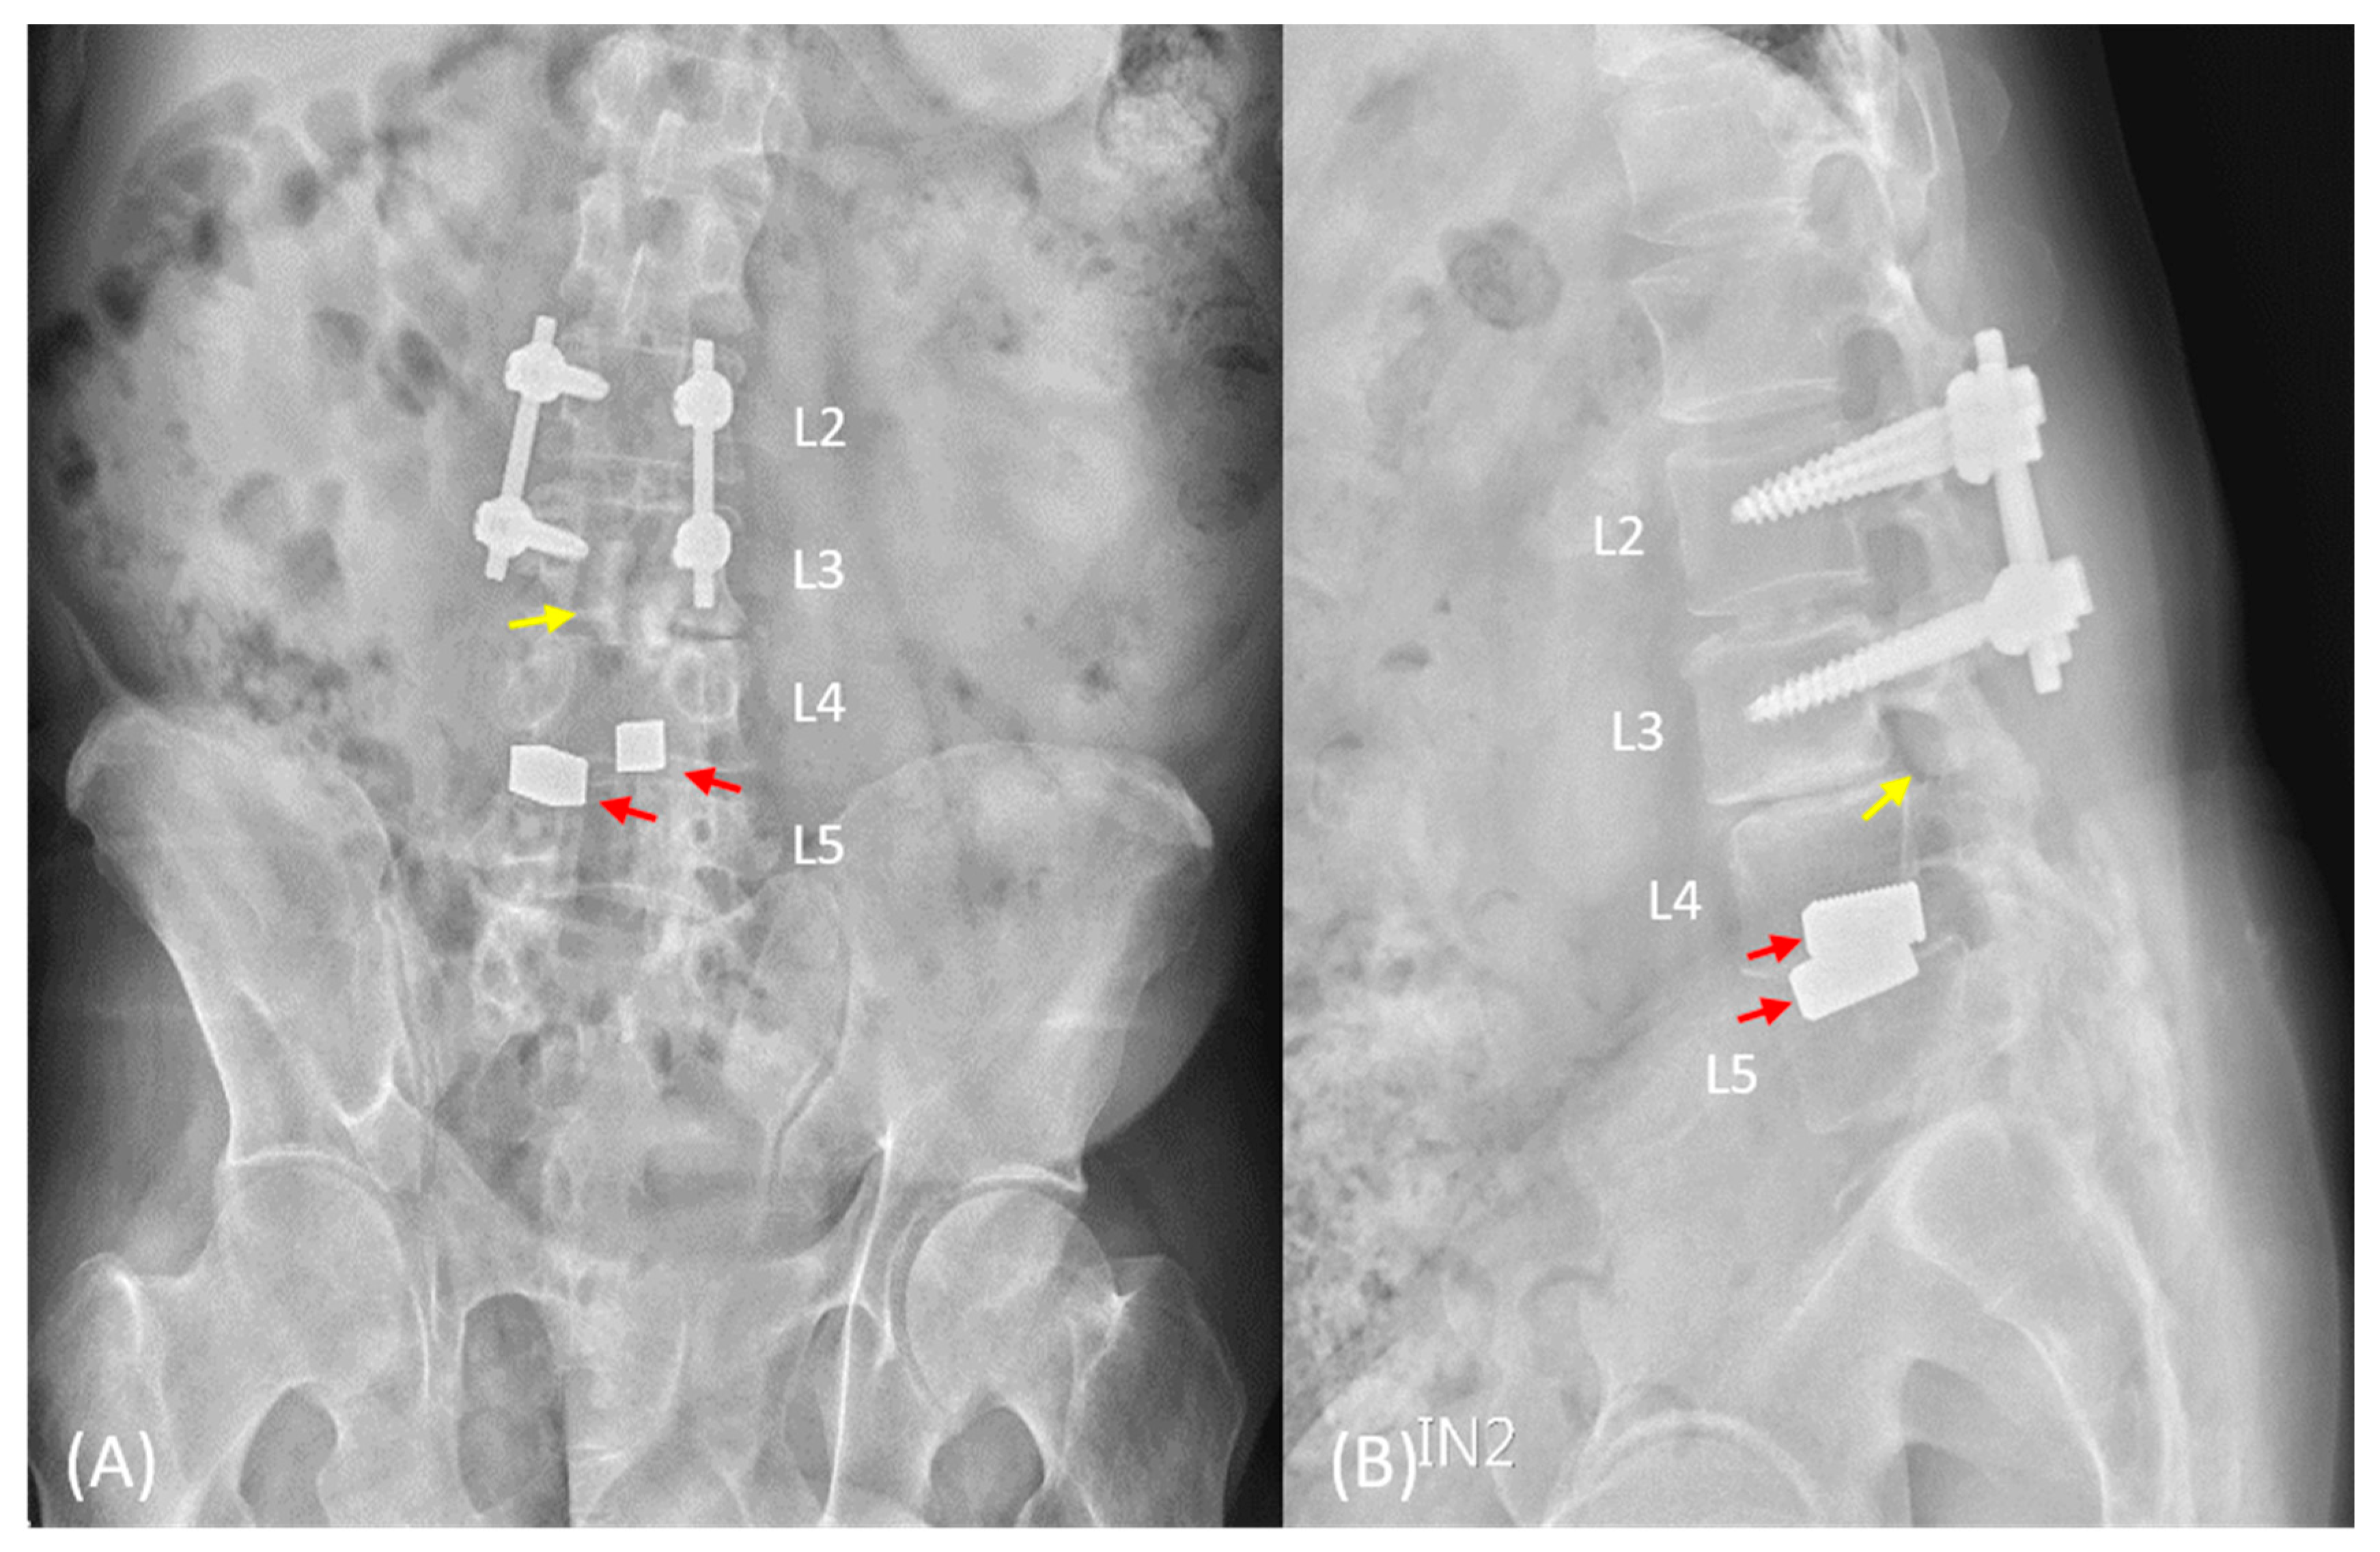

2. Case Presentation